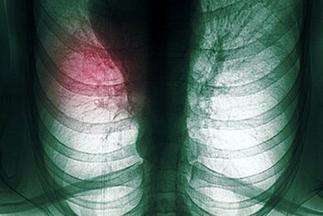

肺癌是我国男性发病率和死亡率最高的恶性肿瘤,并且肺癌的发病率还在持续上升。肺癌治疗目前主要有手术、药物化疗(包括靶向治疗)、放射治疗、免疫治疗、局部姑息治疗和中医药治疗等种类繁多,患者在就医时经常一头雾水,难免有病乱投医,而另一方面医生由于对肺癌疾病的认知不够也可能在一定程度上造成肺癌治疗的延误。为了尽可能延长患者的生命、改善生活治疗,应当把当前最新的、已被证实的最有效的治疗方法结合起来,在确定每个肺癌患者主要的治疗方向后,再为每个患者量身定制具体方法,使每位肺癌患者都得到最佳治疗,所以肺癌治疗规范化下的个体化治疗具有非常重要的意义。

由于肺癌缺乏早期症状及我国总体医疗水平相对落后,目前在我国超过半数的肺癌患者就诊时已经发生远隔转移,失去手术的机会,尽管手术治疗在肺癌所有治疗方法里是最好的,但手术后病人其总体的5年生存率仅在40-50%,手术并不能解决所有的问题。目前肺癌医治是强调以手术为主的综合治疗,有手术条件的患者往往还要在术后补充化疗甚至放疗,或在术前化、放疗后再手术,针对没有手术条件或术后肿瘤复发的病人就要以化、放疗为主,并结合免疫、中医及各种局部减症的治疗手段。